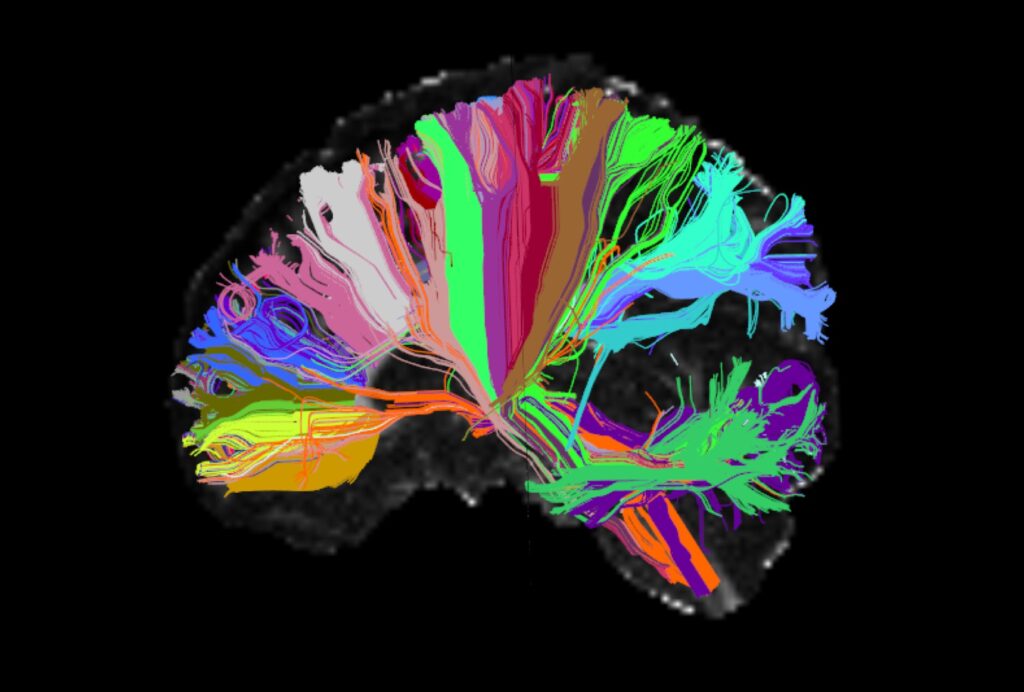

In 1990 President George Bush announced that “a new era of discovery” was “dawning in brain research.” Over the next several decades the U.S. government poured billions of dollars into science that promised to revolutionize our understanding of psychiatric disorders, from depression and bipolar disorder to schizophrenia. Scientists imagined that mental illnesses in the future might be diagnosed with genetic tests, a simple blood draw, or perhaps a scan of your brain. New pharmaceuticals would target specific neurochemical imbalances, resulting in more effective treatments. The 1990s, Bush declared, would be remembered as “The Decade of the Brain.”

This brave new world of brain research also promised to free us of the stigma and discrimination attached to mental illness and addiction for centuries. Localizing psychiatric disorders in the brain would make them chronic medical diseases—like diabetes and high cholesterol—instead of individual moral failings or deficiencies in character. While it was impossible to predict exactly what the future would bring, there was an overwhelming sense that psychiatric science was going to crack the “mystery” and “wonder” of this “incredible organ,” as Bush called it.

Looking back as a psychiatrist and historian today, I find that these hopes feel quaint. They remind me of other misplaced visions of technological futures from the twentieth century: flying cars, pills for a whole day’s nutrition. The reality of psychiatric practice is far less glamorous than the visions of its future that I grew up with. Thirty years later we still have no biological tests for psychiatric disorders, and none is in the pipeline. Instead our diagnoses are based on criteria in a book, the Diagnostic and Statistical Manual of Mental Disorders (often called, derisively, the “bible” of American psychiatry). It has gone through five editions in the last 70 years, and while the latest edition is almost 100 pages longer than the last, there is no evidence that it is any better than the version it replaced. None of the diagnoses is defined in terms of the brain.

How did we end up here? If we have failed to understand psychiatric disorders biologically, what happens when we examine them historically? Two recent books by historians explore the crisis in biological psychiatry, tracing the political, economic, social, and professional factors that led psychiatrists to attempt to pin the reality of mental illness—and the legitimacy of the profession—on the brain. Written by leading historians in the field, these are big books, in heft and scope, that cover two hundred years of the profession’s failures. They reveal that U.S. psychiatry, across its history, has been dangerously susceptible to hype and “cool,” ranging from enthusiasm for brain dissection in the 1890s to the fanfare surrounding neurotransmitters and genetics a century later.

As the asylum transformed from a therapeutic institution into a site for research over the course of the late nineteenth century, thousands of dissections were performed on the bodies and brains of mostly poor patients without their consent. Harrington concludes that they revealed “more or less nothing.” The problem was that neuroanatomists had no idea what they were looking for. The psychiatrist Karl Jaspers summed up these anatomical efforts as a “brain mythology.” Neuroanatomical dissection was a bust.